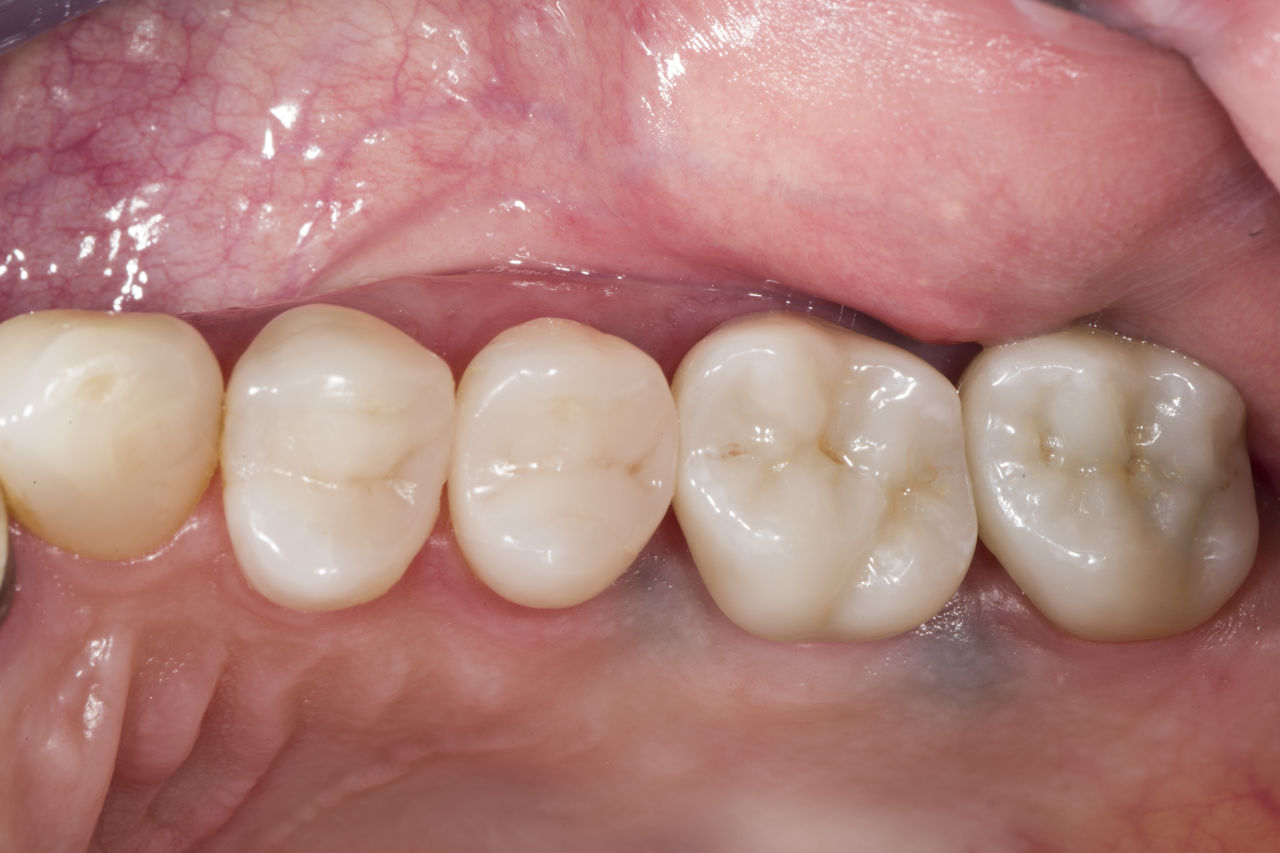

Quadrant rehabilitation

Two CEREC Tessera crowns and two inlays

Within a single visit of four hours the restoration of two crowns and two inlays, which were 15 years old, was carried out. The patient was very pleased with the very good esthetic result.

Before: Insufficient fillings in the second quadrant. The restorations were about 15 years old.

After: Chairside-fabricated crowns made from CEREC Tessera (teeth 26/27). Inlays for teeth 24 and 25 made of composite blocks.